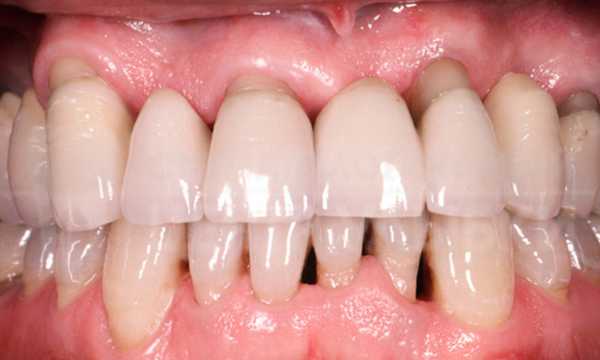

- Абсцессы и флегмоны – острые инфекционные заболевания, отличаются гнойным поражением одного или нескольких областей (клетчаточных пространств), повышением температуры, постоянными ноющими болями, усиливающимися при дотрагивании к пораженной области, плотными отеками (инфильтратами) на лице или шеи.

- Парадонтит – воспаление слизистой полости рта, точнее всего комплекса тканей окружающих зуб. Чаще всего поражается десна в области всех зубов, реже одного-двух. Основная причина – плохая гигиена, затем уже патологический прикус и неправильно леченные зубы, и на последнем месте в ряду причин – хронические декомпенсированные заболевания (напр. сахарный диабет). Проявляется кровоточивостью десен и гиперестезией зубов. В запущенных случаях гной выделяется из под десны, каких либо болевых ощущений обычно нет, может быть болезненность десен при чистке зубов.

Хронический генерализованный пародонтит тяжелой степени.

У данного пациента множественный кариес, пародонтит, переодонтит нескольких зубов, хронические пульпиты, патология прикуса, повышенная стираемость зубов, клиновидные дефекты. Не правильно расположенные нижние зубы мудрости.

Данная ситуация — довольно распространенный в практике случай.